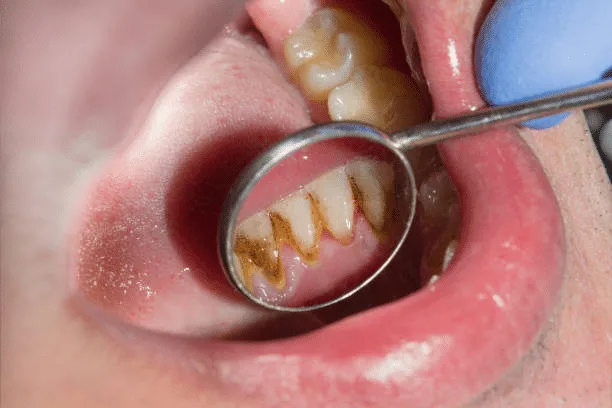

Acute Plaque-Associated Gingivitis

This type of gingivitis is caused by the buildup of dental plaque, a sticky film of bacteria that forms on the teeth. It is characterized by red, swollen gums that may bleed easily, especially during tooth brushing or flossing.